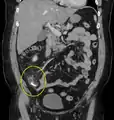

| A fecalith marked by the arrow which has resulted in acute appendicitis. | |

Appendicolith as seen on CT